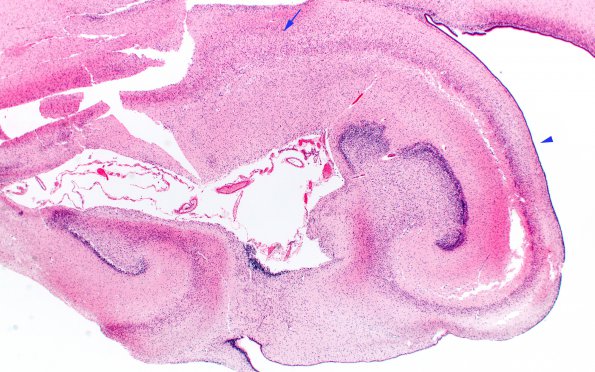

Washington University Experience | VASCULAR | Hypoxia-Ischemia, fetal-neonatal | Pontosubicular necrosis | 2B1 Hypoxia Ischemia, neonatal (Case 2) (PSN) H&E 2X copy

This whole mount of the hippocampus is disrupted but the neurons of the CA1-4 regions appear well preserved (arrowhead) compared to the subiculum (arrow) at this magnification. (H&E)